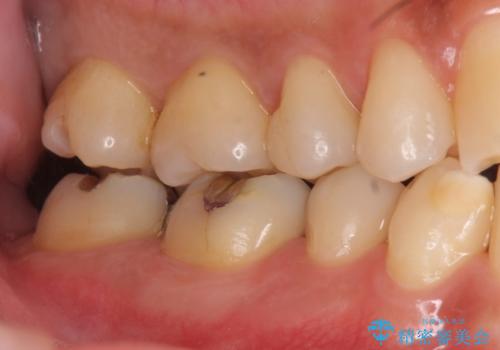

奥歯の虫歯 セラミックインレーに

- 上の奥の虫歯をセラミックインレーで修復しました。

奥歯は力がかかるところであるので、保険適応の白い材料は必ず劣化し、2次う蝕(再度虫歯)になる可能性が非常に高いですので全くおすすめできません。

2次う蝕になり、治療を繰り返していると抜髄(神経を取らないといけない)の可能性が高まります。

治療前後の写真をお見せして説明したところ、非常に喜んでいただきました。

特に自費のインレーの適合(歯にぴったり合っている)はとても良く、虫歯になりにくいです。